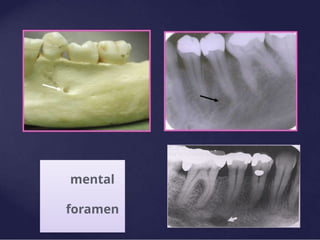

Mental Foramen

► It is the anterior limit of the inferior alveolar

canal.

► It doesn’t appear on every radiograph because

its opening is directed superiorly and posteriorly.

► It may be round, oblong, slit-like or very

irregular and partially or completely

corticated.

► The foramen is seen about half way between

the lower border of the mandible and the crest

of the alveolar process usually in the region of

the apex of the second premolar.

► Misinterpreted as a periapical pathosis.

mental

foramen